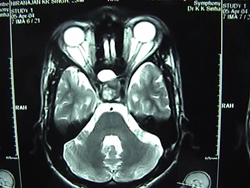

Pituitary Tumor Surgery